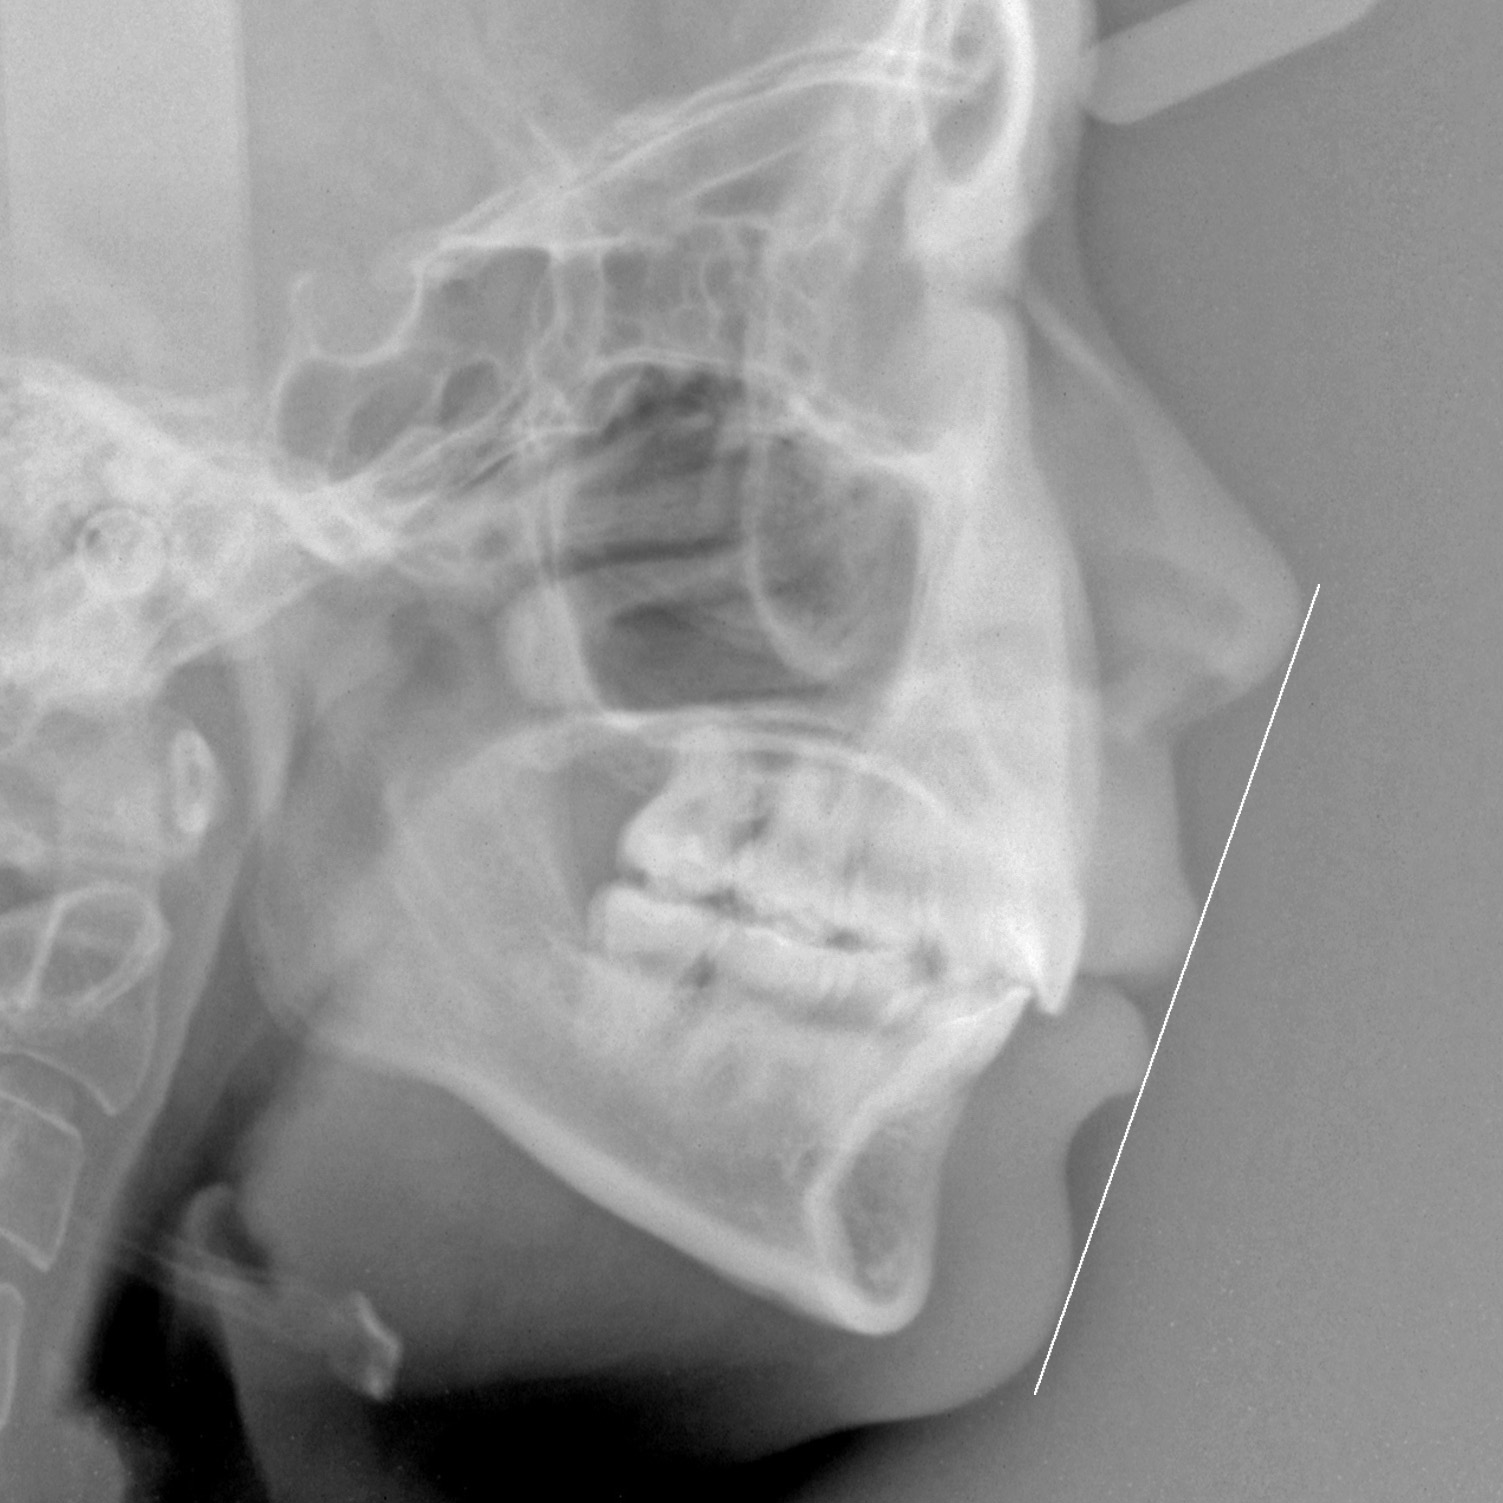

新着情報 1426 治療後セファロ側面 – コピー Tweet 投稿日 : 2025年04月07日(月)カテゴリー : コメントを残す コメントをキャンセルメールアドレスが公開されることはありません。 * が付いている欄は必須項目ですコメント 名前 * メール * サイト 「 出っ歯、口もと を 治してほしい」 28歳 女性 治療期間30か月(重度の上顎前突症) ≫